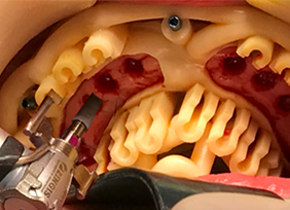

新一代口腔种植导板

西泰克双导(TwinGuide)数字化种植辅助系统,利用自研的TG-System系统、TG-Design设计软件、结合TG-Ai系统和设计团队为牙医提供安全可靠的种植方案,并通过3D打印生成产品。

双引导更精准

术野更开阔

冷却更充分

西泰克双导(TwinGuide)数字化种植辅助系统,利用自研的TG-System系统、TG-Design设计软件、结合TG-Ai系统和设计团队为牙医提供安全可靠的种植方案,并通过3D打印生成产品。